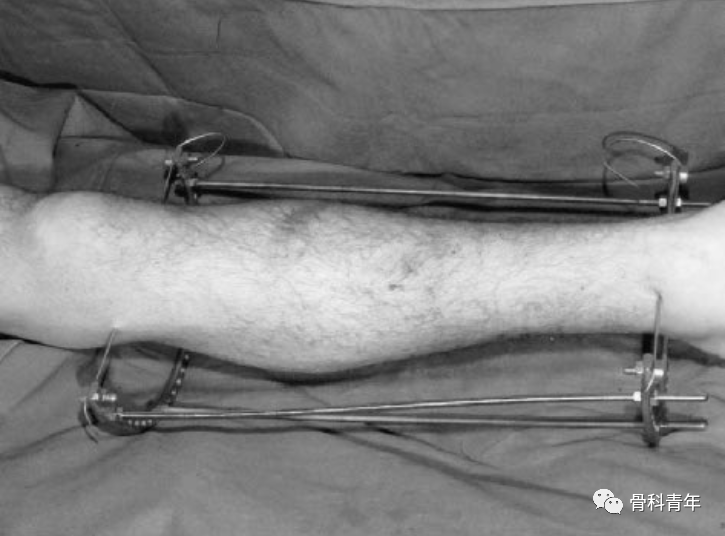

2019年JOT期刊上,国外学者改良了该方法,采用碳纤维外固定架,结合张力钢丝维持复位,取得了良好的效果。

通过在胫骨平台下方1cm,平台偏后部置入一根钢丝,另一根钢丝置入踝关节软骨下骨处,钢丝连接外侧2/3碳纤维环形架,施加110kg拉力形成张力。由于钢丝非中心置入,因此在轴向撑开时,骨折断端可能会向后成角,需要在中部后方垫消毒巾,并巾钳固定。

该外架为碳纤维,术中不影响透视,且该2/3外架,将连接杆置于小腿后方,给髓内钉的内外置钉留出空间。